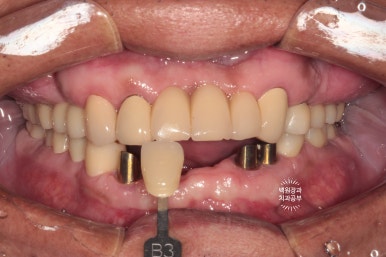

shade guide를 사용하여 치아의 색상을 측정해 봅니다.

기존에 사용하고 계시던 위 앞니의 보철물이 B3 색상에 가까웠기 때문에, 그 색상으로 제작하기로 결정!!

치아의 색상을 결정할 때는 환자 안모의 피부톤도 감안하여서 정해야 합니다.

어두운 색상의 피부를 가진 60대 환자분에게 어울리는 치아 색상으로 정해보았어요. 너무 하야면 가짜같아요...

대망의 치료 완료!!!!!

보철물이 모두 완성되었어요.!!!

처음 이를 뽑기 시작한 때부터 정확히 9개월이 지난 시점입니다.

비용의 절감을 위해 기능적으로 문제가 없었던 위 앞니 보철물은 그대로 사용하고 계신 상태라

그 부분이 조금 부족한 느낌은 있지만,

새로 만든 치아들은 아주 조화로운 모양과 색상을 보여주고 있네요!!